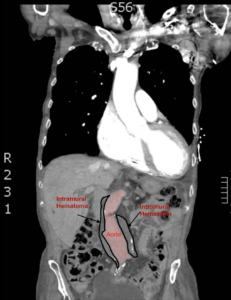

Bedside ultrasound revealed an abdominal aortic aneurysm (AAA) with concern for dissection vs thrombus/hematoma due to an area of echogenicity within the lumen of the vessel, since normal blood vessels (including the aorta) have lumens that are uniformly anechoic. An intimal flap concerning for dissection appears as a hyperechoic stripe within the lumen of the vessel on ultrasound, often with a hypoechoic and/or anechoic area appreciated underneath the flap, indicating a separate area of blood flow. If this visualized area is of significant size, color doppler can be used to confirm blood flow on both sides of the flap. Given his bedside ultrasound findings, the patient underwent emergent computed tomography scan and was found to have an enlarged infrarenal abdominal aortic aneurysm, with acute intramural hematoma, extending into bilateral common iliac arteries.

An abdominal aortic diameter greater than 3.0 cm is classically defined as an AAA. Risk factors associated with developing a AAA include male sex, smoking, advanced age and a positive family history.1,2 Furthermore, given that approximately 25 percent of patients with thoracic aortic aneurysm will also be found to have an abdominal aortic anuersym,3 this patient was at an elevated risk. Overlap in histochemical changes are observed in patients with AAA and TAA, and there may be a common cellular link that explains a similar pathogenesis.4 Formation of thrombus is the product of decreased laminar flow at the periphery of a dilated aorta, which causes blood stagnation.5

This patient was evaluated by vascular surgery in the ED and considered not an optimal surgical candidate. Because he was found to have concurrent renal impairment, any amount of intra-operative contrast dye would be detrimental and advised against. During his admission he was cautiously diuresed and ultimately discharged home with outpatient vascular surgical follow up for elective repair.